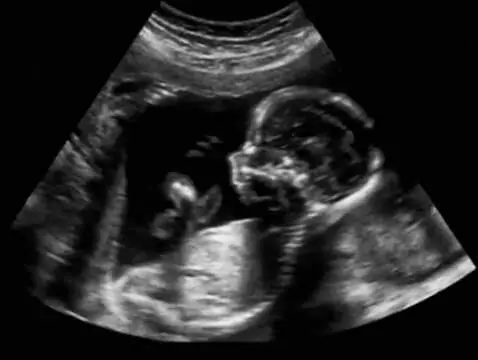

O tym, czym jest, kiedy należy je wykonywać oraz jakich informacji możemy oczekiwać po badaniu USG połówkowym, dowiesz się z tego artykułu.

Badania prenatalne przeprowadzane w I i II trymestrze ciąży pozwalają na wykrycie wielu wad u rozwijającego się dziecka. Nieinwazyjne badania prenatalne są bezpieczne zarówno dla matki, jak i...